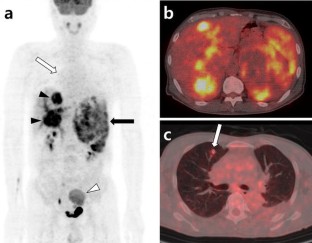

Adrenocortical oncocytoma is a very rare tumor, which is not malignant and nonfunctioning in most cases. We report a case of a 53-year-old male with a 9.8 cm sized hyperfunctioning, well-encapsulated adrenal mass, which exhibited by high FDG uptake on a PET/CT scan. The patient had complained of symptoms of Cushing’s syndrome for 4 months. Laparoscopic adrenalectomy was performed and the mass was pathologically confirmed as adrenocortical oncocytoma of uncertain malignant potential. Four years after surgery, the tumor recurred with distant metastases, which was proven by subsequent biopsy. 18F-FDG PET/CT also showed hypermetabolism in the recurred tumor and multiple metastatic lesions. Adrenocortical oncocytoma of borderline malignant potential with high FDG uptake may require long-term follow-up with clinical, hormonal, and imaging evaluations.